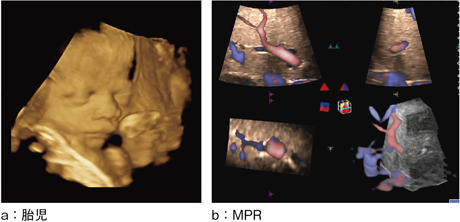

High Density Renderingとは,高速な3D/4DのVolume Rateを実現する新エンジンである。3D/4D画像が高速かつ高画質に得られる(図9)。4Dプローブにより構築した3D画像の管腔を内側から観察する“Fly Thru”は,膵管,胆管,尿管,血管,乳管,消化管など幅広い領域で期待が持たれる新機能である(図10)。

図9 4Dイメージ

図10 Fly Thru